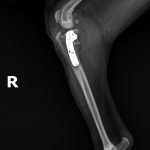

雑種犬(22kg)の左前十字靭帯断裂に対するTPLO術(脛骨高平部水平化骨切術)☑